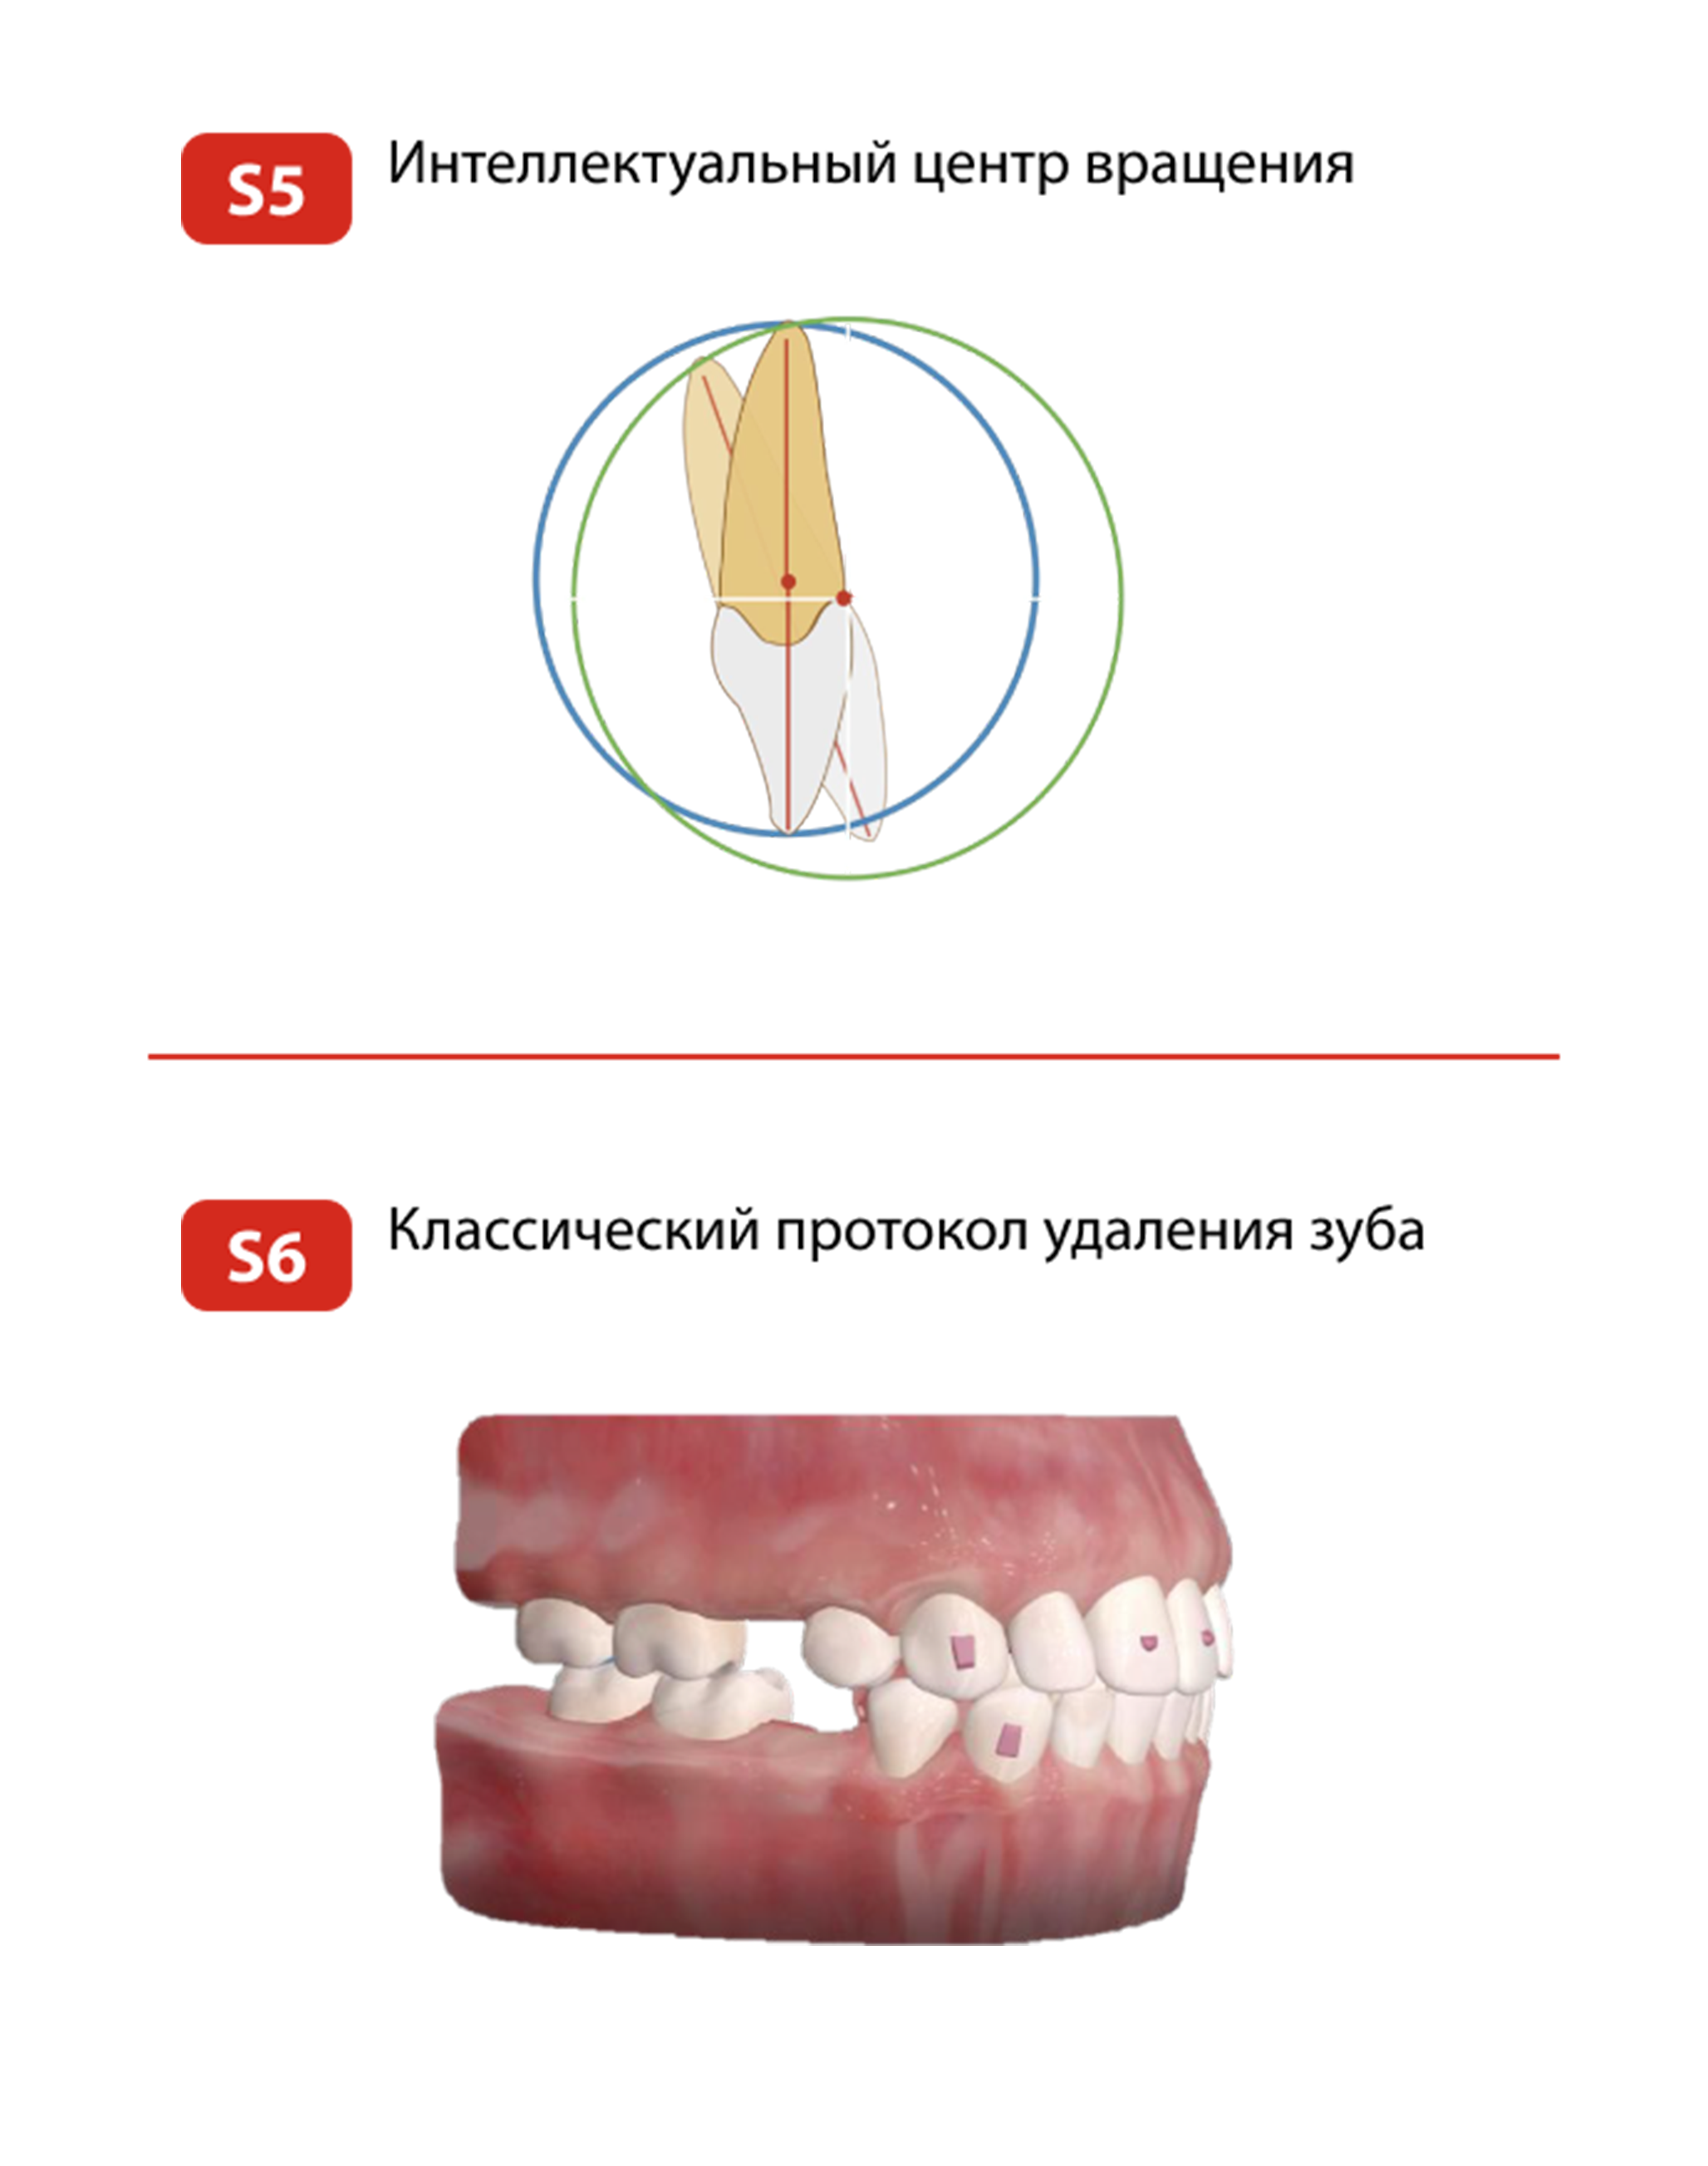

ТРЁХСЛОЙНАЯ ТЕХНОЛОГИЯ ПРОИЗВОДСТВА ПЛАСТИН

C 2006 года мы опробовали материалы множества производителей и к 2016 году

приняли решение взять контроль качества на себя и открыть собственное производство

Трёхслойная технология производства пластин